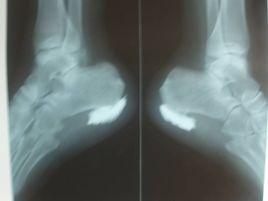

6、三個月後x光片顯示自體骨組織顯影清晰,骨生長因子材料完全降解,負重行走無疼痛感。 “微創增高術”由於創傷小,不影響行走,生活能自理。該方法不需要損壞原來的骨骼部位,在安全可靠的前提下增高身體。

這種手術是目前比較主流的,更為安全的增高手術。但是缺點是:見效不明顯。其原理是採用微球囊組織撐開技術,將足跟緻密的軟組織撐開腔隙,把納米磷酸鈣膠原基人工骨材料注入跟骨骨膜下,這種材料表面可提供適宜的環境促進膠原和礦物的沉積以及自身成骨細胞的粘附,成骨細胞粘附於種植體表面,並且進行爬行替代性生長, 納米磷酸鈣膠原基人工骨材料逐漸降解,最終會完全的消失,被自身骨組織完全的替代。從而達到人體增高的目的。